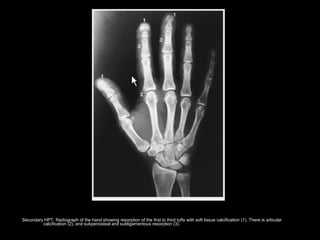

Secondary HPT. Radiograph of the hand showing resorption of the first to third tufts with soft tissue calcification (1). There is articular

calcification (2), and subperiosteal and subligamentous resorption (3).